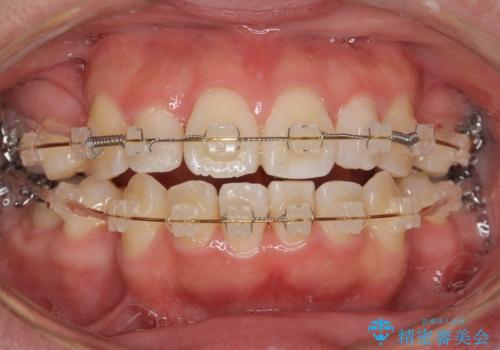

全顎的に歯並びにがたつきがあり、上の側切歯(上顎両側2)は生まれつき小さい歯(矮小歯)でした。

矯正治療後、矮小歯をセラミッククラウンにより理想的な歯の大きさに仕上げました。

※矯正治療は井上副院長が行っております。